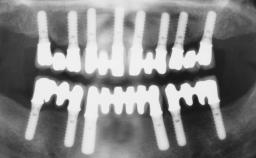

A 31-year-old man presented to our clinic 30 days after a motor vehicle accident in which he had suffered a dentoalveolar fracture in the anterior maxilla, including avulsion of teeth 12 and 11 and luxation of tooth 21. He was first treated on the night of the accident in a small city hospital with no oral and maxillofacial surgeon on the staff. A wired retention had been applied and the teeth repositioned to the best of the clinicians’ abilities. When he first presented to our care, the patient showed extrusion of teeth 12 and 11 associated with gingival recession due to bone loss in the anterior maxilla, and the stainless steel wires were still present.

# of Implants 3

Type of Implants One-Piece|Reduced-Diameter

Bone Augmentation Horizontal|Staged|Vertical

Augmentation Materials Autogenous chips|Autogenous block(s)

Prosthesis Type FDP